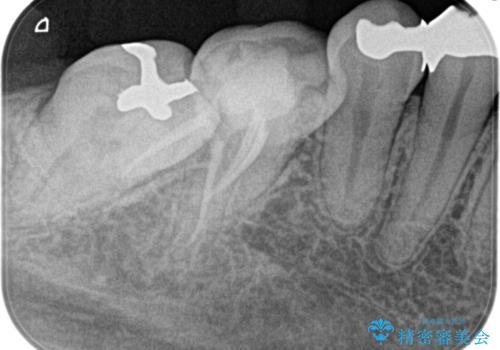

【根管治療】昨日から眠れないぐらい歯が痛い

- 昨日から夜も眠れないぐらい痛いことを主訴に来院されました。

検査の結果、不可逆性歯髄炎の診断とし根管治療を行なっております。

- 精密根管治療(イニシャルケース,大臼歯):122,000円、ファイバーコア:22,000円費用は治療当時の料金となります